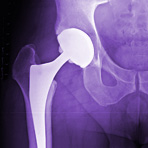

Der Gerinnungshemmer Apixaban (Eliquis®) hat in einer der zwei zugelassenen Indikationen vom Gemeinsamen Bundesausschuss GBA einen geringen Zusatznutzen gegenüber der Standardtherapie attestiert bekommen, und zwar zur Thromboseprophylaxe bei Patienten, die eine neue Hüfte bekommen. Damit folgte der GBA der Einschätzung des Instituts für Qualität und Wirtschaftlichkeit im Gesundheitswesen. In der zweiten Indikation, der Thromboseprophylaxe bei Kniegelenkoperationen, sah der GBA einen Zusatznutzen jedoch nicht belegt. Damit starten die Hersteller Pfizer und Bristol-Myers-Squibb mit einer geschwächten Position in die Preisverhandlungen mit den Krankenkassen.

Das IQWiG kam in seinem Gutachten zur frühen Nutzenbewertung im März zu dem Schluss, dass zwar unter der oralen Therapie mit Apixaban seltener Thrombosen in den tiefen Beinvenen nach Hüft- und Kniegelenkoperationen auftraten als unter einer Prophylaxe mit dem subkutan gespritzten Enoxaparin. Lungenembolien beugte jedoch das niedermolekulare Heparin bei knieoperierten Patienten besser vor, daher hier die Bewertung «kein Zusatznutzen».